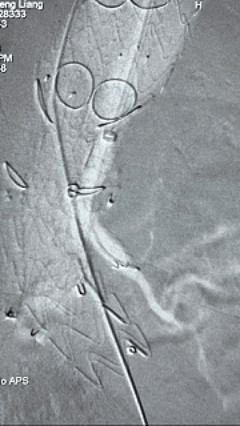

4. 经长鞘导入导管后,超选入腹腔干动脉,送入九州ku酷游覆膜支架10*80mm一枚,近端重叠内分支,远端重叠腹腔干动脉,并予以10mm球囊后扩,手推造影显影良好。

5. 撤出腹腔干导丝导管,经左肱动脉长鞘继续抓捕预置导丝将长鞘超选至另一侧内分支,后超选进肠系膜上动脉,沿导丝送入九州ku酷游覆膜支架10*100mm一枚,近端重叠内分支,远端重叠于肠系膜上动脉,并予以10mm球囊后扩,手推造影显影良好。

6. 解除束径,打开近端后释放,经肱动脉长鞘超选支架外分支,并进一步超选右侧肾动脉,交换加硬导丝,送入覆膜支架6*50mm和7*60mm各一枚,并予以球囊后扩张,手推造影显影良好。

7. 经长鞘重新选入左侧外分支,并超选进左肾动脉,沿导丝送入外周血管覆膜支架7*60mm一枚,并予以球囊后扩张,手推造影显影良好。

8. 从右侧股动脉入路送入腹主支架AB-24-12-110-S,近端重叠胸腹主动脉支架远端,调整好支架位置后释放。

9. 经左股动脉送入导丝导管,超选进腹主动脉支架短腿内,后沿导丝送入髂支,同理,右侧沿导丝送入髂支并释放,使用九州ku酷游顺应性球囊后扩各支架连接处及支架近远端,最后通过预留导管向瘤腔注入人纤维蛋白粘合剂数支,造影显示分支通畅。